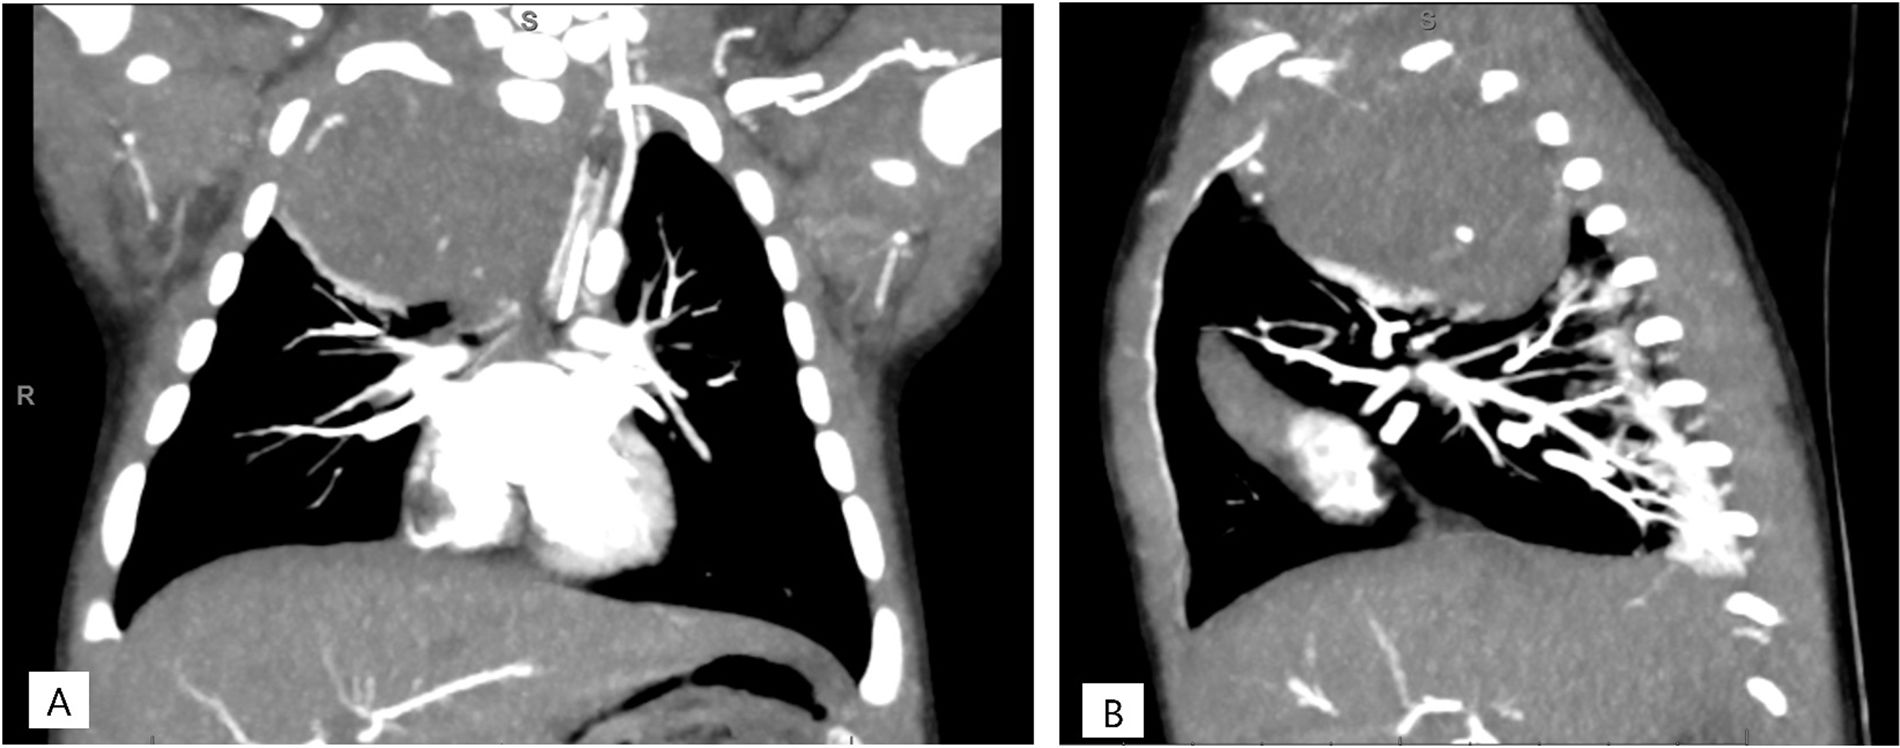

La radiografía de tórax mostraba una opacidad completa en el lóbulo superior derecho (fig. 1), mientras que las ecografías pulmonares seriadas eran normales (fig. 2A). La ecografía torácica realizada desde el plano supraclavicular mostraba una consolidación bien definida sugestiva de masa torácica (fig. 2B y vídeo 1) que se evidencia en la TAC (fig. 3). La biopsia confirma el diagnóstico de neuroblastoma congénito.

TAC torácica con administración con contraste intravenoso. Masa en mediastino posterior de 4,6×4,3×6,3cm con realce heterogéneo y pequeñas calcificaciones en su interior que ejerce efecto masa desplazando estructuras adyacentes y comprimiendo el lóbulo superior derecho. A)Corte coronal. B)Corte sagital.